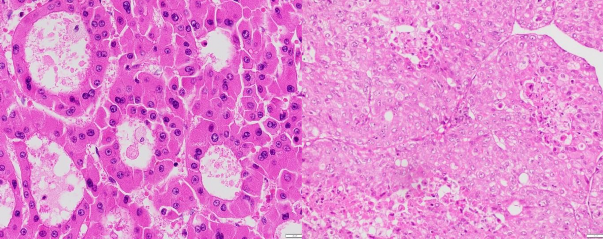

Ảnh 3.1. (A) UTBMTBG thể giả tuyến với các tế bào u sắp xếp dạng giả tuyến hoặc nang (HE x 200, mã số: 3837-18). (B) UTBMTBG thể đặc với các tế bào u đứng thành mảng đặc, không rõ xoang mạch (HE x 100,

mã số: 688)